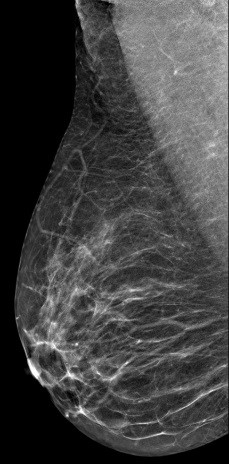

病史:患者,女53岁,体检超声检查提示右乳结节。

V-preview图像:

DBT图像:

常规2D 图像上象限似见小结节,边缘有小毛刺,还可见粗大血管影穿过,CC位上又没发现异常影像,DBT检查后在合成2D图像上表现同常规2D,但在DBT图像的上象限可以清楚见到一小结节,呈分叶状,边界较清楚。

结合DBT考虑病灶为BI-RADS 4A病变。

右乳纤维瘤。